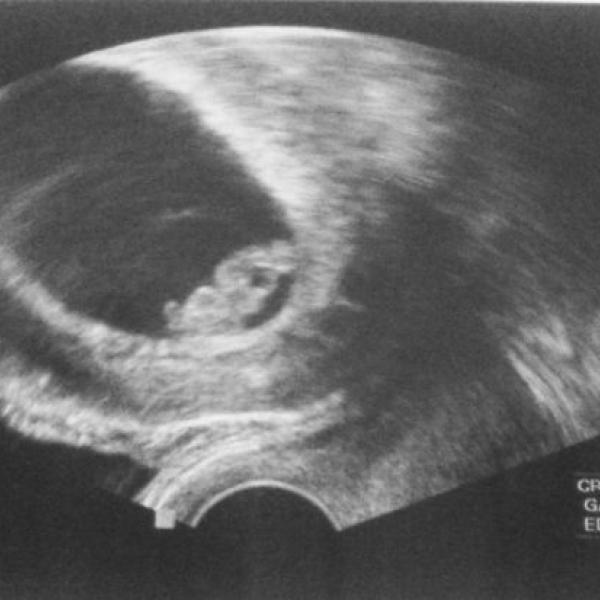

Manasa 23.02.2012 Detail Ahojky, chtěla jsem se v pondělí přihlásit jako snažilka, jenže jsem si večer udělala testík a bylo to. To jsme fakt doma nečekali. Komentáře jsou momentálně nedostupné. Děkujeme za pochopení.